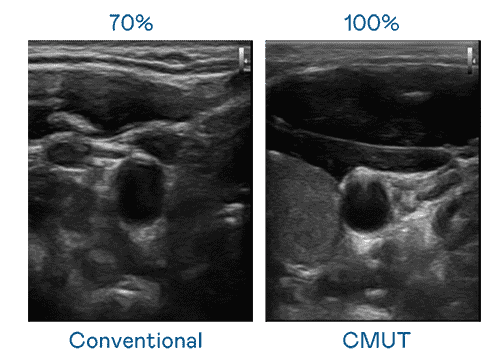

CMUT 技术是一种用电容式微机电元件来产生超音波讯号的技术。。。与传统 PZT 压电式技术相比,,,CMUT 频宽增加 30%,,更宽频的超音波讯号让影像解析度大幅提升,,,,是实现高影像品质医疗超音波扫描、、、促进精准医疗发展的关键技术。。。

超音波影像的解析度高低,,,,首先取决于探头能发出的讯号频宽。。优游UB8 CMUT 可提供高清晰的超音波讯号,,,,提供高频宽、、、高灵敏度、、、、影像纹理细节更高的超音波影像,,协助医护人员缩短影像判读时间及利用精准的医疗影像进行诊断。。。。